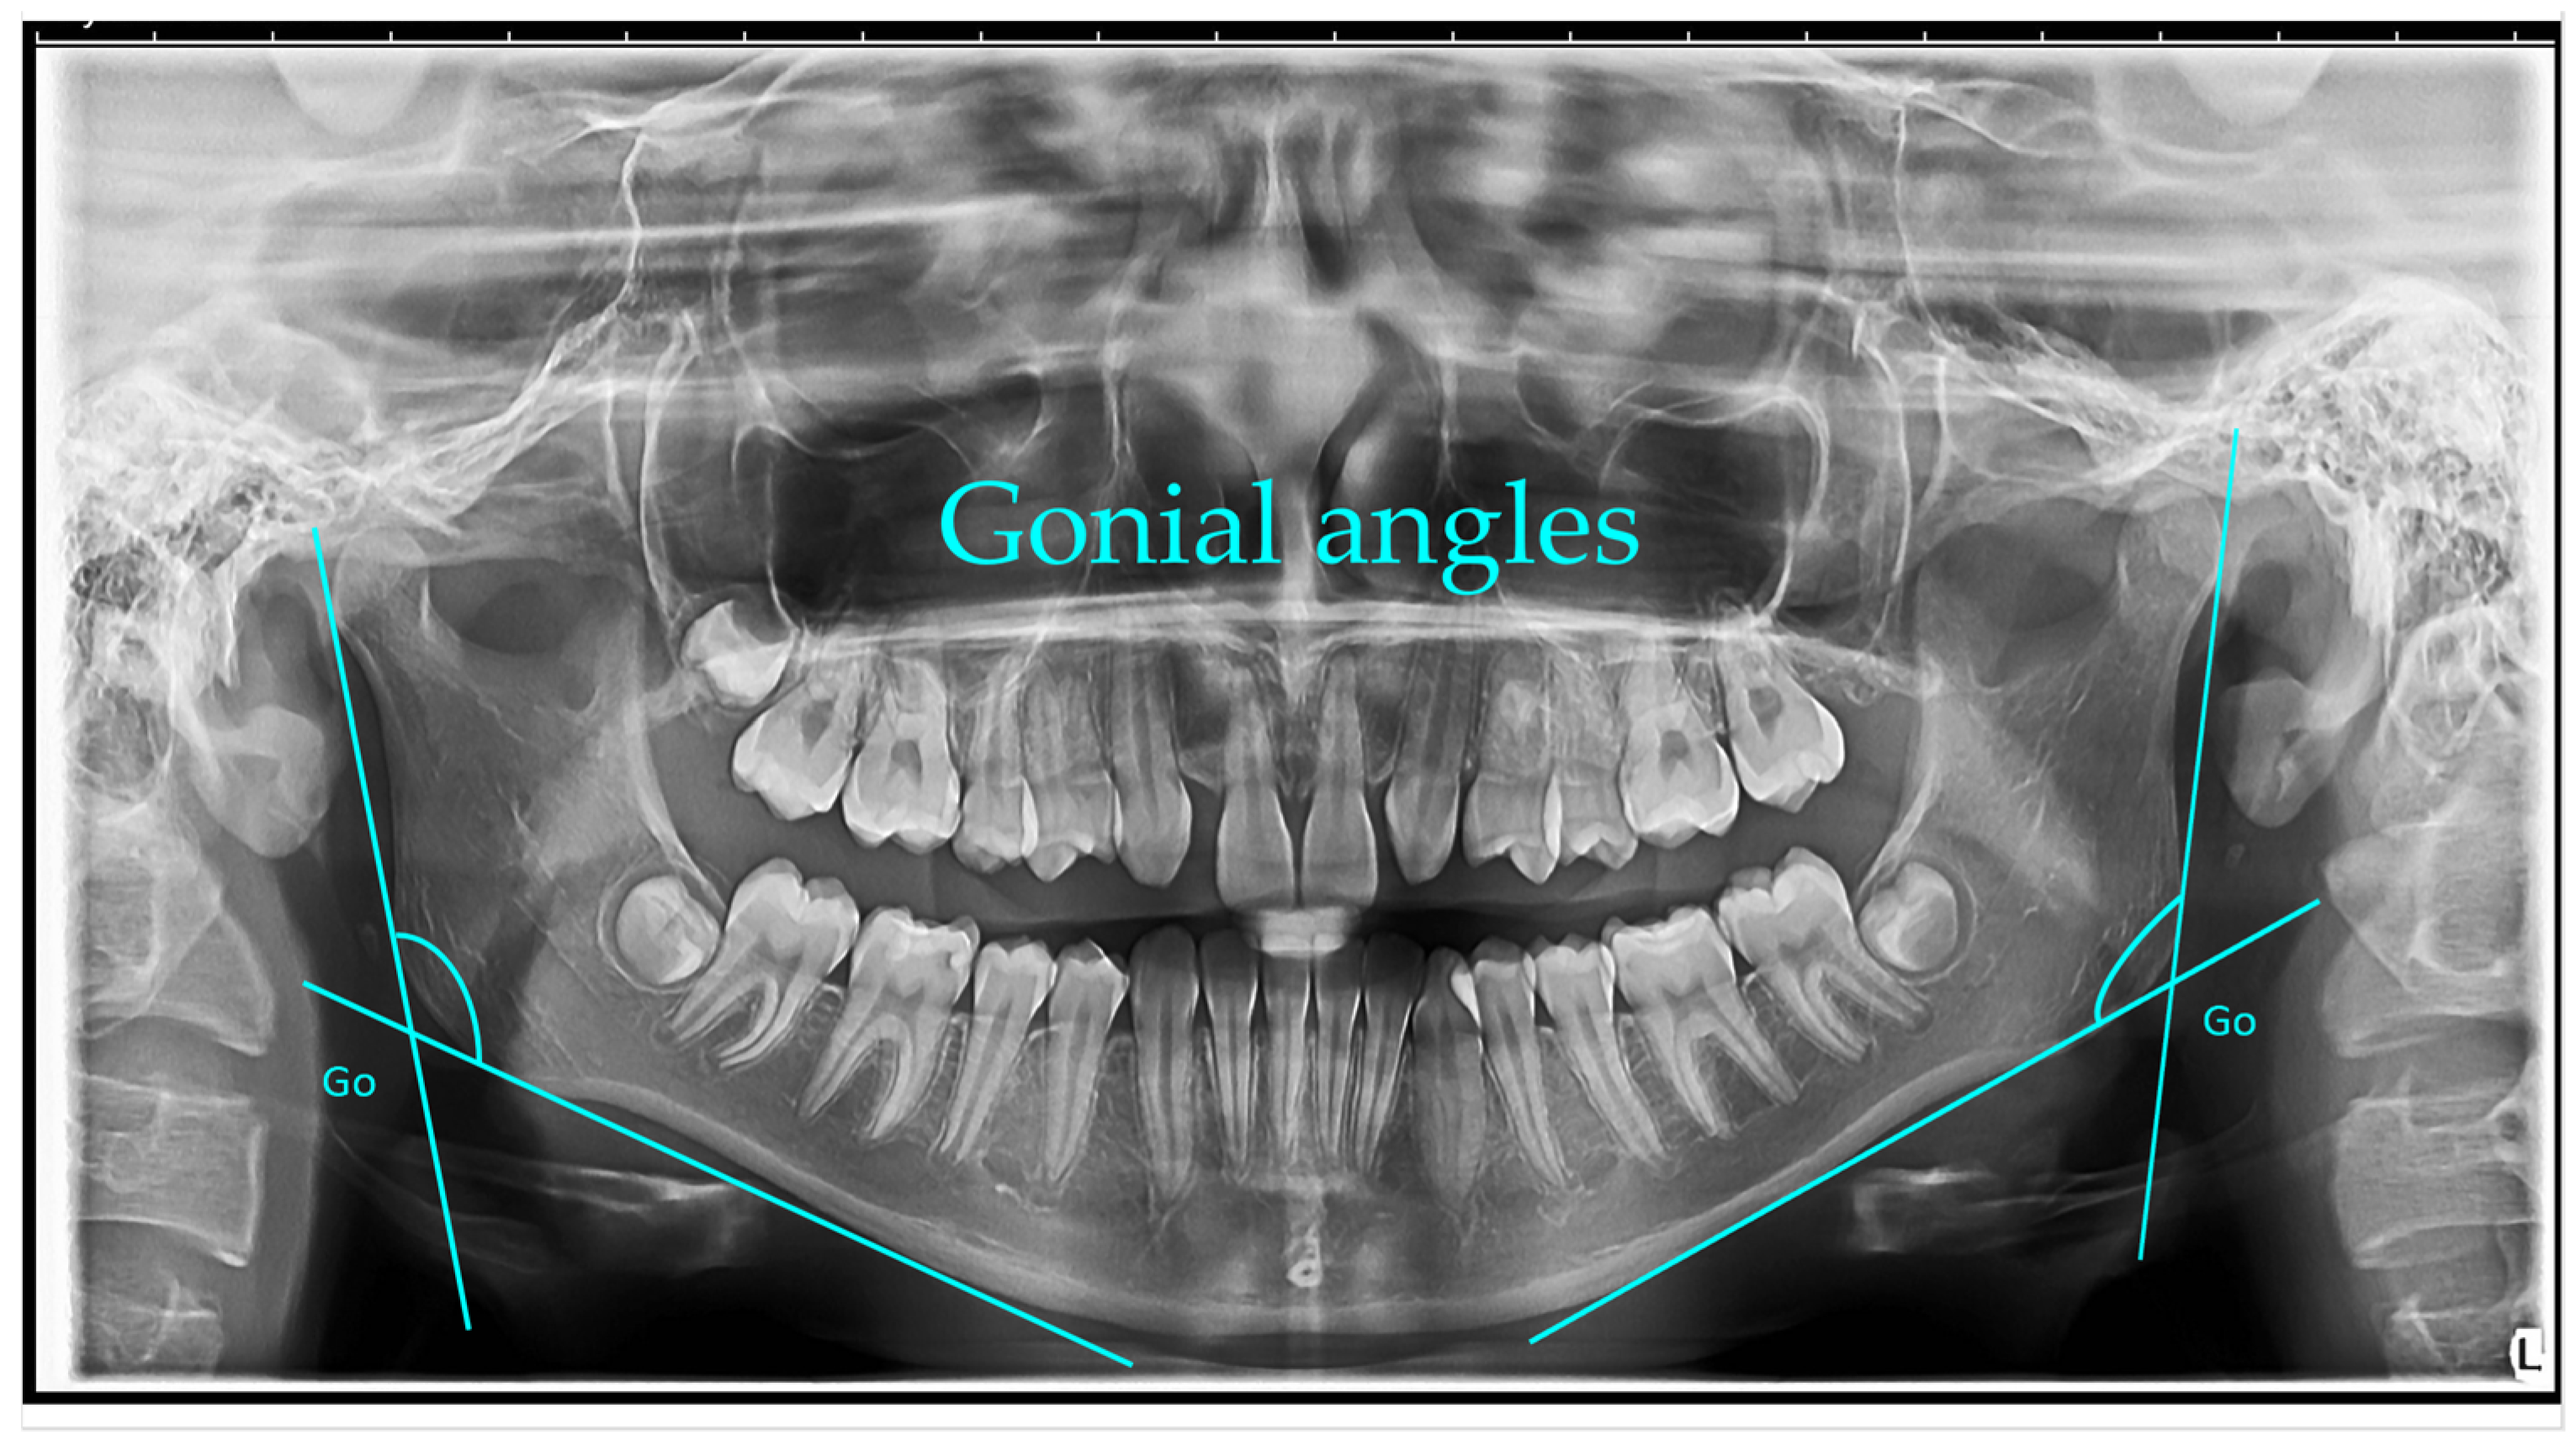

Gonial angle (left and right)—measured as the angle formed between a line along the lower border of the mandible passing through the condyle and a line along the posterior border of the ascending ramus. The mean gonial angle obtained from panoramic radiograph measurements was 122.74° (SD = 1.00°) overall, 122.84° (SD = 0.80°) for males, and 122.74° (SD = 1.00°) for females [1].

Gonial angle: The gonial angles were measured following the method described by Mattila et al. A line was digitally drawn on each panoramic radiograph tangential to the most inferior point at the gonial region and along the lower border of the mandibular body. A second line was traced tangential to the posterior borders of the ramus and the condyle. The intersection of these two lines defined the gonial angle, which was measured on the right or left side, depending on which provided the clearest image.

Panoramic radiograph (orthopantomogram) illustrating the measurement of bilateral gonial angles. The gonion (Go) point was identified on both the right and left mandibular borders, and lines were drawn along the posterior border of the ramus and the lower border of the mandible to form the gonial angle. Both right and left gonial angles are indicated for comparative analysis (Figure 1).

Figure 1. Bilateral Gonial Angle Measurement on OPG. Go (gonion)—the most posterior, inferior, and lateral point on the mandibular angle. Lines were drawn along the posterior border of the ramus and the lower border of the mandible, intersecting at the gonial angle (°). Both right and left gonial angles are displayed for comparative analysis. Note: Images represent direct screenshots exported from the WebCeph® AI platform. Landmarks and measurement lines were automatically generated and manually verified by the authors.